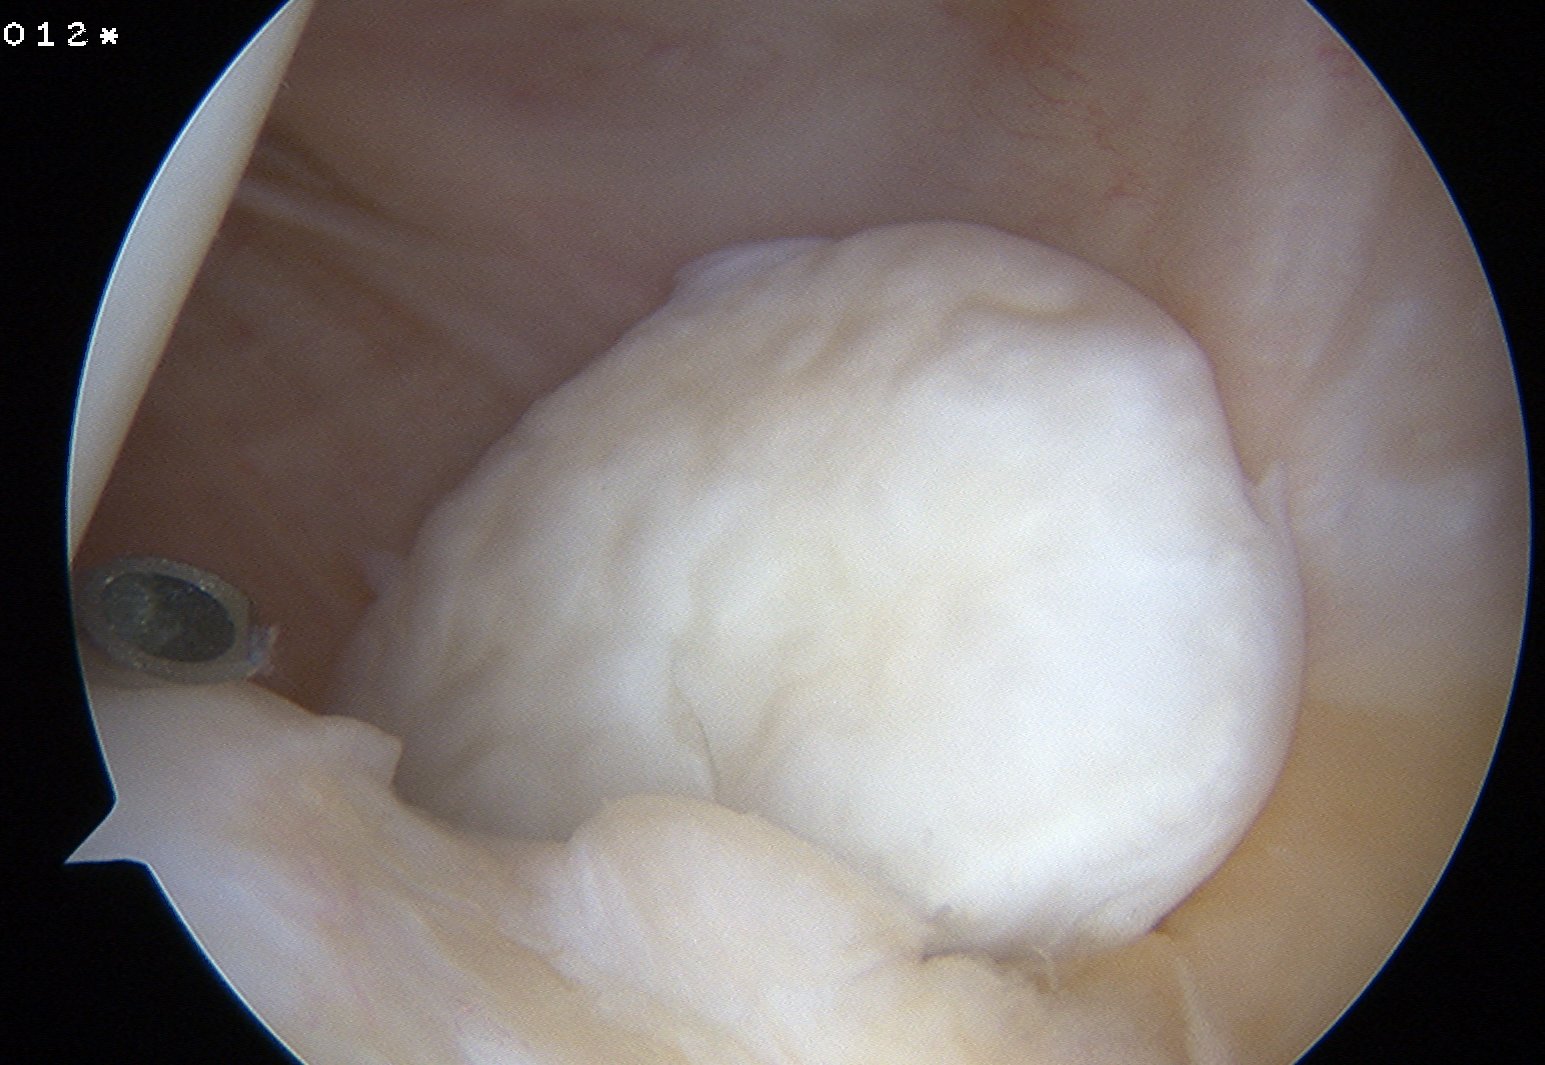

2. Lateral Gutter

- common here

- often need to retrieve via Superolateral portal

3. Posteromedial corner

If can't find loose body

- always look here

Technique

- put camera in standard portal

- use probe to lift PCL up

- push camera gently into interval between MFC and PCL

- need to make posteromedial portal to retrieve loose body

4. Posterolateral corner

- change camera to medial portal

- use probe to lift up ACL

- push camera through